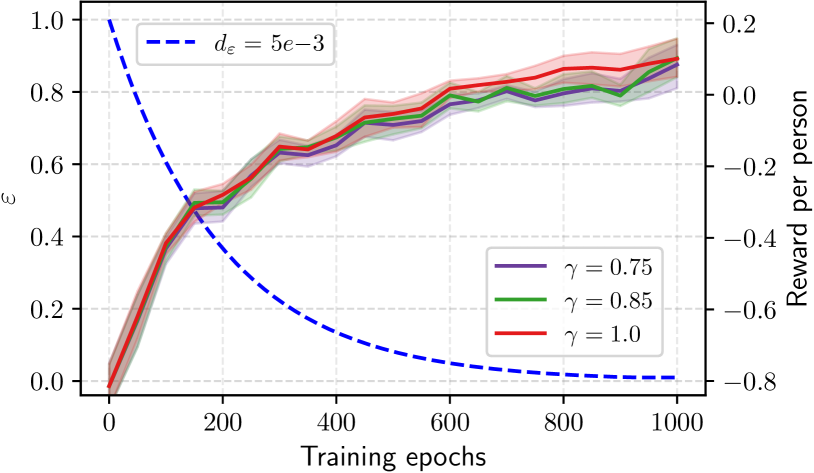

For the -greedy policy, we conducted the experiment where was selected from the set , , . Each setting was repeated with random seeds. With different decayed curves, the training policies converged yet at different training times. The convergence of training in any exploration-exploitation strategy serves as preliminary evidence of the effectiveness of our proposed reward function in identifying an optimal policy. By comparing the learning curve of decaying greedy policies during epochs training, we concluded by choosing , illustrated in Figure 6, as the most appropriate value to define the exploration-exploitation process within an acceptable training time.

Besides, an ablation study about the impact of the discount factor on learning progress was expressed in Figure 6 with similar exploration decaying. Our results showed that the values of for discounting future rewards was inefficient and even harmed the performance. was chosen for all the following experiments.